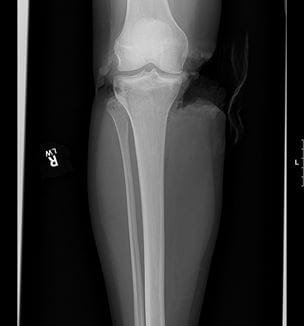

Limb-Saving Surgeries Restore Leg of Teen Injured in Devastating Waterskiing Accident

Innovations in Cardiovascular Medicine & Surgery | Summer 2021